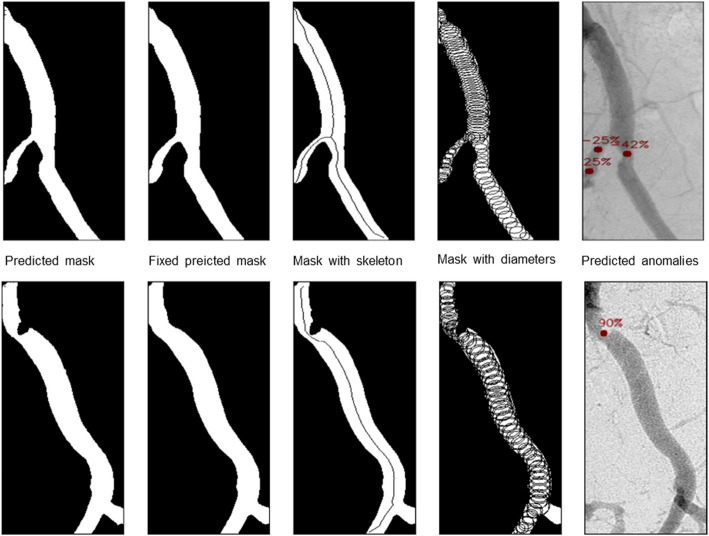

Background: This retrospective study evaluates the diagnostic performance of an optimized comprehensive multi-stage framework based on the Segment Anything Model (SAM), which we named Dr-SAM, for detecting and grading vascular stenosis in the abdominal aorta and iliac arteries using digital subtraction angiography (DSA).

Materials and methods: A total of 100 DSA examinations were conducted on 100 patients. The infrarenal abdominal aorta (AAI), common iliac arteries (CIA), and external iliac arteries (EIA) were independently evaluated by two experienced radiologists using a standardized 5-point grading scale. Dr-SAM analyzed the same DSA images, and its assessments were compared with the average stenosis grading provided by the radiologists. Diagnostic accuracy was evaluated using Cohen's kappa, specificity, sensitivity, and Wilcoxon signed-rank tests.